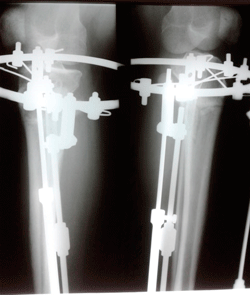

Дата операции - 18.09.2020

Дата снятия аппаратов - 25.11.2020

Срок сращения - 60 дней.